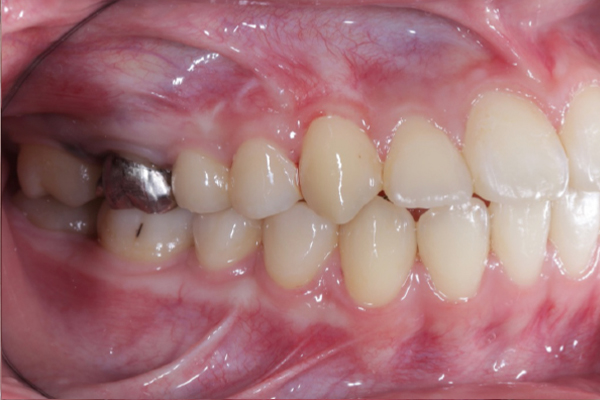

AFTER

2年間にわたる矯正治療お疲れさまでした。決して楽な治療では無かったと思いますが最後まで治療を行うことができました。前歯がしっかり咬んでいない患者様は咬み合わせが不安定なことが多く、前歯の咬み合わせが空いてしまう可能性があります。今後は、後戻りの定期的な確認、虫歯予防をおこなっていきましょう。